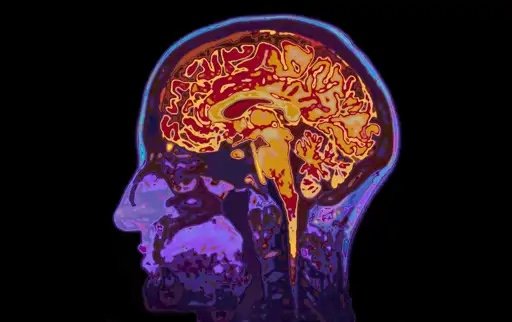

¿Puede una actividad recreativa en mitad de la naturaleza retrasar el envejecimiento cerebral? Según un equipo de científicos del Rotman Research Institute de Canadá, la